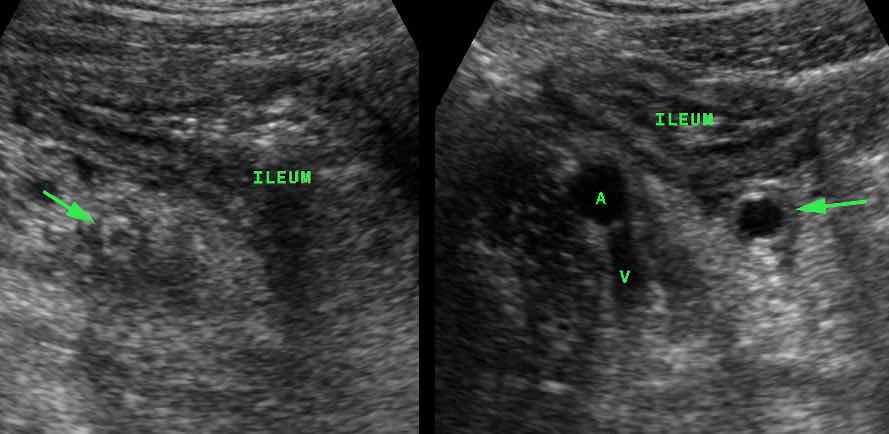

Một bẫy khác là viêm đầu ruột thừa, trong đó tình trạng viêm chỉ khu trú ở đầu xa của ruột thừa.

Nếu chỉ quan sát được phần gần bình thường (mũi tên trong A), trong khi đầu xa (mũi tên trong B) bị che khuất bởi hơi ruột, có thể dẫn đến chẩn đoán âm tính giả. (a và v = động mạch và tĩnh mạch chậu)

Viêm ruột thừa (mũi tên) gây dày thành thứ phát của hồi tràng lân cận. (A và V = động mạch và tĩnh mạch chậu)